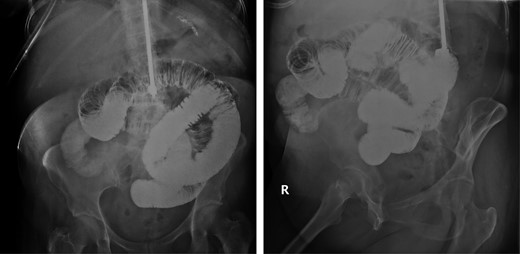

She showed minimal signs of improvement after 24 h. A small bowel follow through with Gastrografin was ordered. This study identified a complete obstruction in the mid-segments of the small bowel corresponding to the distal jejunum, proximal ileum (Fig. 1). An exploratory laparotomy was performed on post-admission Day 2 due to the findings of a complete obstruction. During the operation, the small bowel appeared hyperemic and dilated. The small bowel was inspected from the ligament of Treitz to an area of transition. At this point, the distal small bowel was decompressed, and an intraluminal mass was palpated. A small bowel resection with a side-to-side anastomosis was performed. The gross specimen was opened and contained an intraluminal mass with the characteristics of a lipoma (Fig. 2). Pathologic evaluation of the specimen showed a 1.5 × 1 × 1 cm3 submucosal lipoma with a small area of overlying ulceration and no evidence of malignancy (Fig. 3). The rest of her hospital course was complicated by a fascial dehiscence requiring retention suture placement. She was discharged on post-operative Day 18.

Small bowel follow-through with gastrograffin showing completed obstruction after 8 h in the mid-right lower mesogastric region.